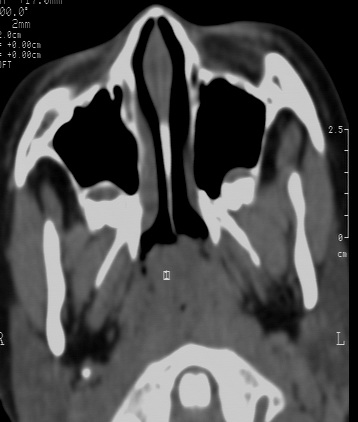

女 5岁 夜间打鼾数年 本人第一次遇到这样的病人,不知是不是鼻咽增殖体肥大?需不需要做手术,请同行给予指导。

典型的鼻咽增殖体肥大

鼻咽腔顶壁及后壁软组织明显肿胀,厚度约2.5cm,鼻咽腔气道轻度狭窄,加之临床病史,支持腺样体肥大。

还可以用鼻咽侧位片测量鼻咽顶部增殖体的厚度和鼻咽腔的宽度,以两者比率来判断儿童增殖体是否肥大。正常时两者比率≤0.60;当比率为0.61~0.70属中度肥大;比率≥0.71属病理性肥大。